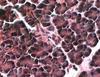

what is pictured

longitudinal section of skeletal muscle